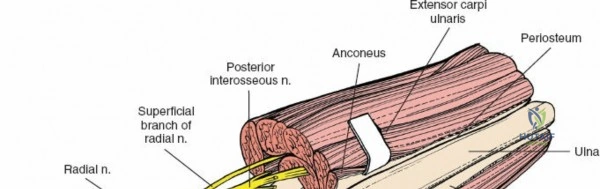

Incise the deep fascia of the forearm in line with the skin incision. The initial goal is to identify the medial border of the brachioradialis as it courses down the forearm. It is a common pitfall to search for this border too far laterally. At the level of the elbow, the brachioradialis is expansive and extends almost halfway across the anterior forearm. It is surprisingly easy to mistake the plane between the brachioradialis and the extensor carpi radialis longus for the correct intermuscular plane.

To confirm the correct plane, look for the superficial branch of the radial nerve. This sensory nerve runs on the undersurface of the brachioradialis muscle. Once the true medial edge of the brachioradialis is found, develop the plane between it and the pronator teres (proximally) or the flexor carpi radialis (distally). Retract the brachioradialis laterally, taking care to keep the superficial radial nerve attached to its undersurface to protect it from traction injury.

The posterior interosseous nerve is the single most important structure left vulnerable during exposure of the proximal radius. A branch of the radial nerve, the PIN dives into the supinator muscle through the Arcade of Frohse. It travels obliquely and spirally around the radial neck and proximal shaft within the substance of the supinator. In approximately 25% of patients, the nerve comes into direct contact with the posterior periosteum of the radial neck. Therefore, any blind placement of retractors around the posterior aspect of the proximal radius is strictly contraindicated, as it can easily crush the nerve against the bone, resulting in devastating loss of finger and thumb extension.